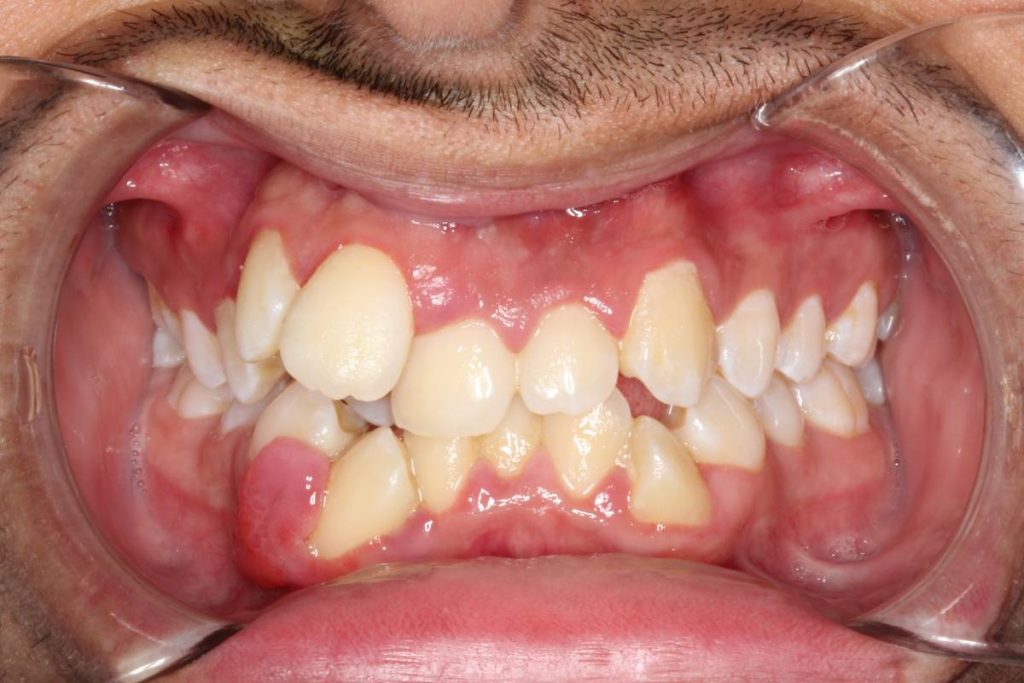

Pero su situación era compleja: después de valorar todos los apuntes, y según nuestras mediciones, tenía una desviación de la línea media de 12 mm y una discrepancia óseo-dentaria de 14 mm. Estos números quizás no os digan nada, pero dentro de nuestro trabajo son una barbaridad para que una boca realice de forma correcta todas sus funciones.

Nuestras sospechas se confirmaban. El caso 139 residente en Torremolinos presentaba 2 circustancias que suelen ser comunes a este tipo de situación aguda y que hacen los tratamientos sean más complejos: macrodoncia generalizada y apiñamiento con asimetría debido a una discrepancia óseo-dentaria. Vamos por partes y explicaremos primero qué significa cada cosa.

Imagen completa del paciente: puede comprobarse todos los problemas que hemos comentado anteriormente.

La discrepancia ósea dentaria es la diferencia entre el espacio óseo habitable (espacio disponible) y el tamaño dental (espacio requerido). Cuando es positiva, es decir, cuando hay más espacio disponible, suele generar diastemas (separación de dientes). Es fácil deducir qué sucede en caso contrario: si la discrepancia es negativa causa apiñamiento y/o maloclusión.